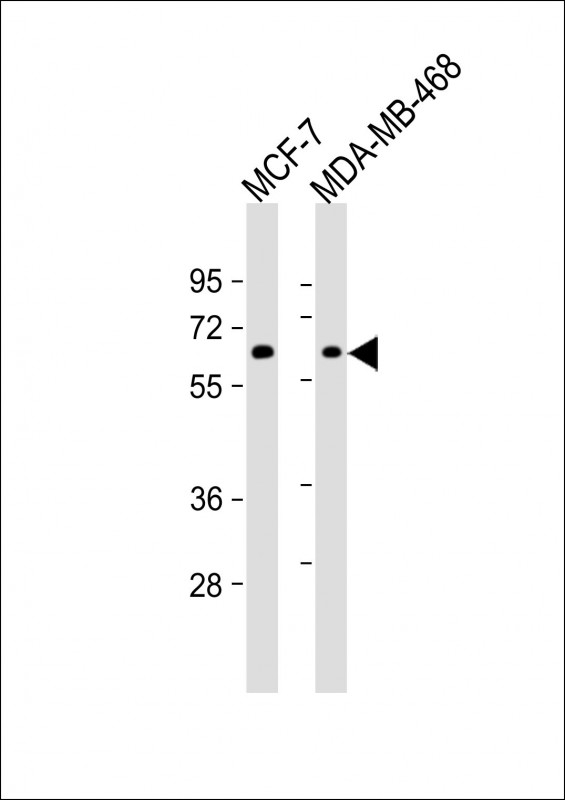

| WB Predicted band size | 148kDa |

| Species Reactivity | Human |